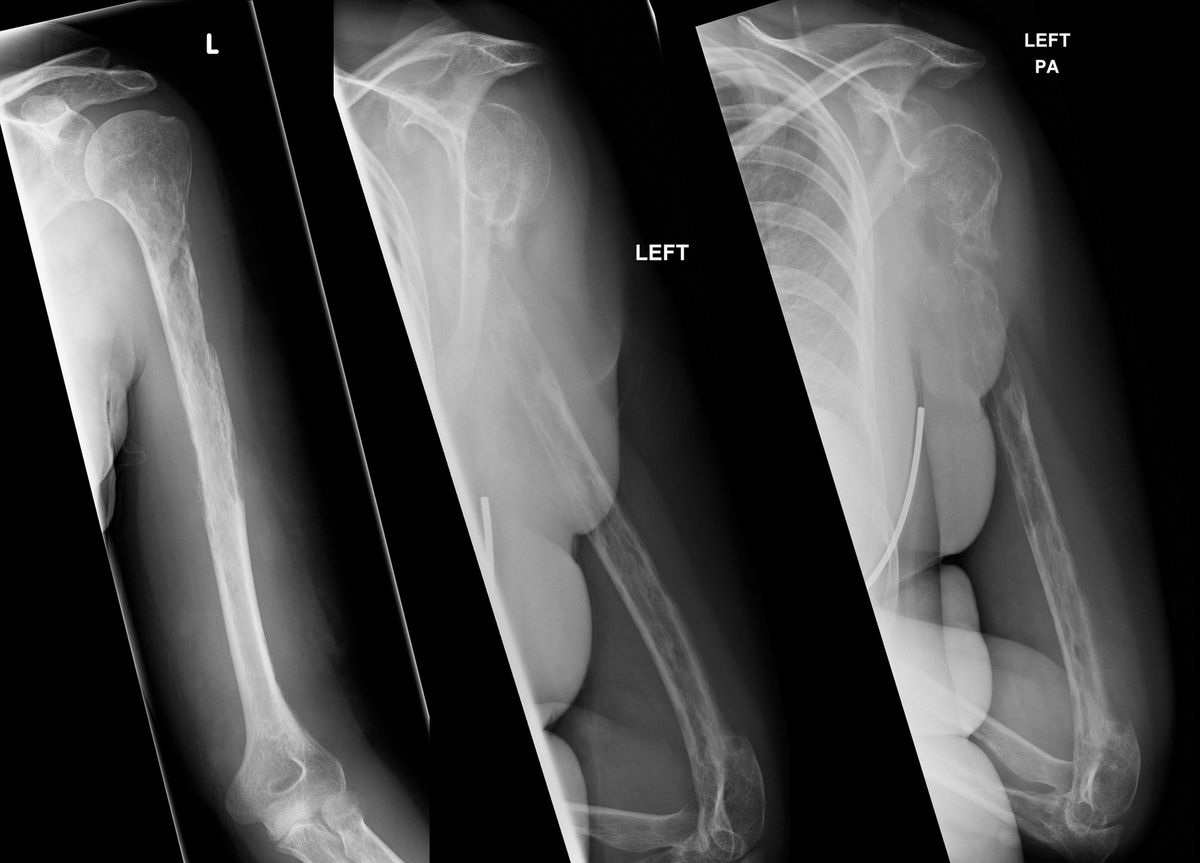

Fibula Definition Anatomy Function Facts Britannica